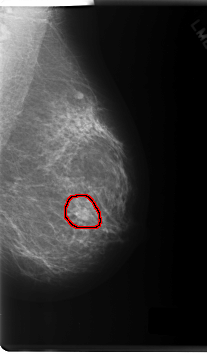

FILE: C_0165_1.LEFT_MLO.OVERLAY

TOTAL_ABNORMALITIES 1

ABNORMALITY 1

LESION_TYPE MASS SHAPE ROUND MARGINS SPICULATED

ASSESSMENT 5

SUBTLETY 5

PATHOLOGY MALIGNANT

TOTAL_OUTLINES 1

BOUNDARY